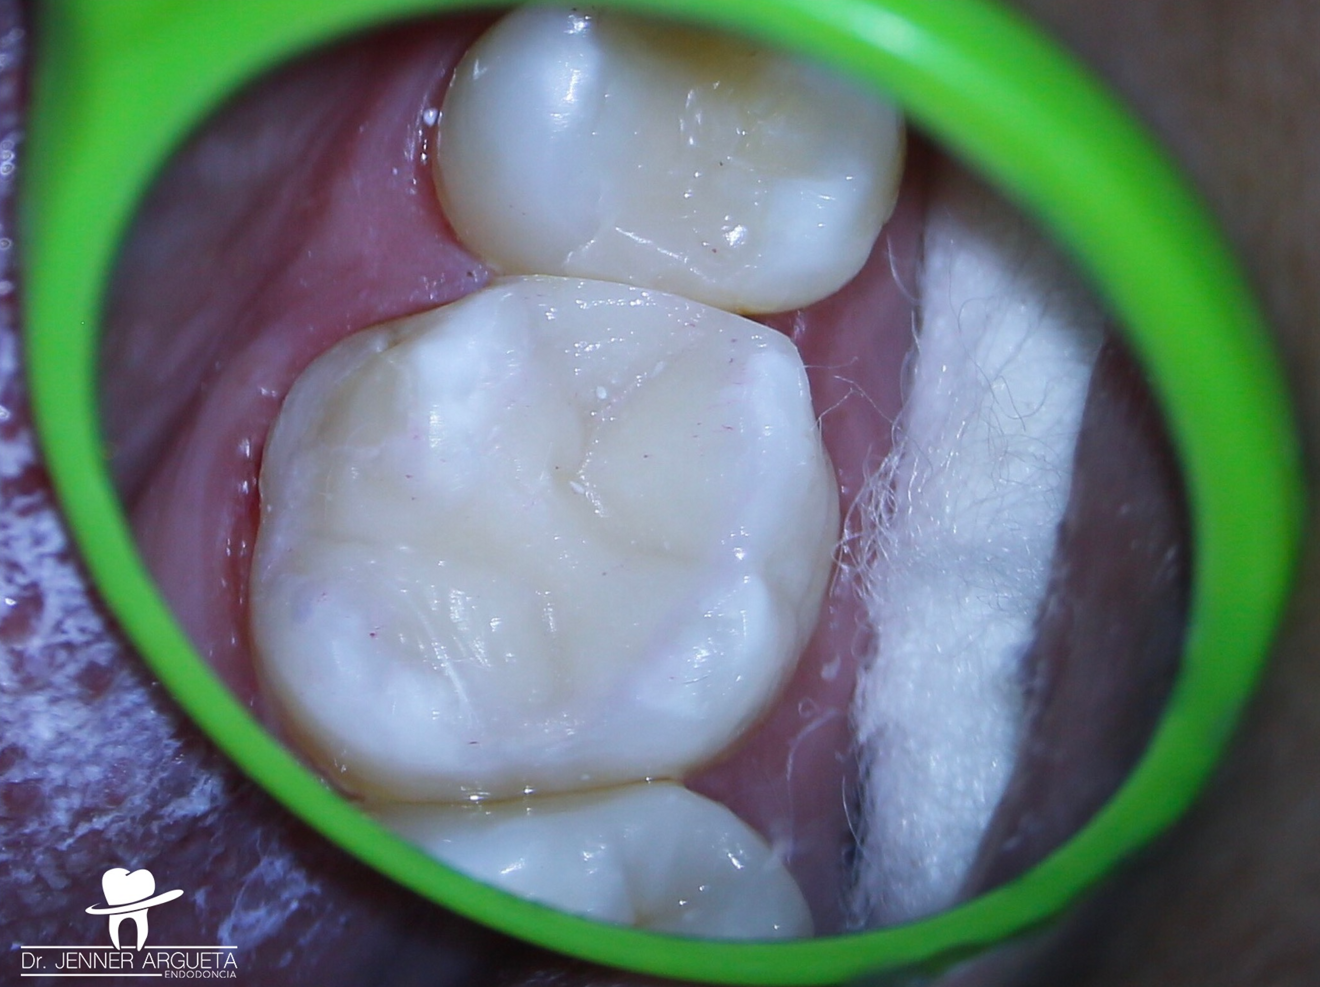

Fig. 1: Tooth #16 with temporary restoration. Total isolation prior to the removal of caries. (All images: Dr Jenner Argueta Endodoncia)

The patient attended reporting short-term pain in tooth #16 (Fig. 1). Through radiography, clinical assessment and an analysis of the patient’s clinical history, reversible pulpitis was diagnosed, and a deep Class II temporary restoration was found (Fig. 2).